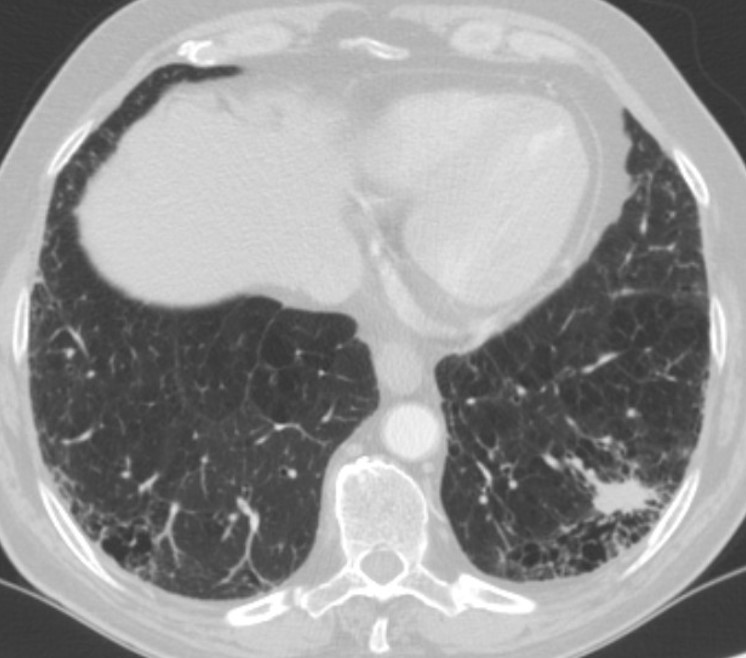

This video shows a posterobasal (S9+10) left lower lobe segmentectomy for a lepidic adenocarcinoma of 1.7 cm without nodal involvement. Arterial segmental division can be easily achieved when the pulmonary artery is divided by identifying the central branch of the artery (between the upper segment artery A6 and the anterior segment artery A8). Division of the vein requires careful identification of segmental veins for the upper segment, anterior segment, and posterobasal segments. There is a high frequency of variation in the intersegmental veins, so special attention should be focused to clearly determine which of the veins drains S9+10 in order to preserve venous drainage for the remaining segments and avoid segmental infarction [4].